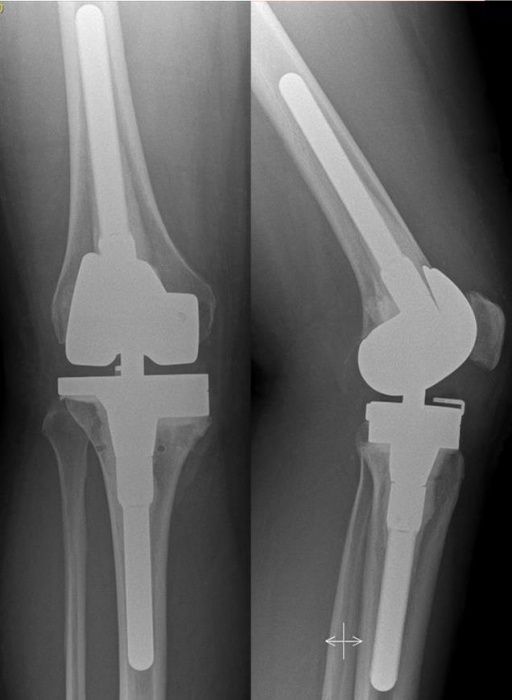

Anschließend wird eine Röntgenuntersuchung durchgeführt inklusive einer Patella-Aufnahme und einer Ganzbeinaufnahme, um die Achse des Beines vermessen zu können.

Ergänzend kann eine Computertomographie durchgeführt werden, um die Implantat-Position bestimmen zu können und Hinweise auf eine Lockerung zu erhalten. Eine Knochenszintigraphie kann ebenfalls Hinweise auf eine Lockerung geben.